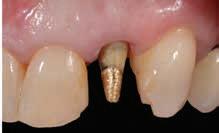

Clinical

management of vital and non-vital discolored tooth preparation stump shades: A clinical case series

Read this article in full at: https://onlinelibrary.wiley.com/doi/full/10.1111/jerd.13184

Objective

Traditional and modern-day laboratory techniques can be used to mask vital and non-vital discolored teeth.

Clinical Considerations

Two clinical case reports are presented showing different treatment approaches to differing clinical scenarios of partial coverage veneer and full coverage crown restorations, respectively.

Conclusions

Case: A 43-year-old Caucasian male patient presented with a history of trauma to his maxillary central incisor teeth, which had discolored over time. His chief complaint was not only the discoloration of the central incisor teeth but also the shape, form, and facial contour that had been attempted with composite resin restorations. (A) After crown removal of #7, the metal post was covered with a white composite resin core material; (B) A gold post foundation restoration was used on tooth #10; (B) Stump shade photographs were taken after tooth preparation; (C) The intaglio surface of the crown restorations with the white opaque liner added short of the cervical margin; and (D) Extraoral smile view of the patient demonstrating esthetic integration of the crown restorations.

Feldspathic ceramics should be considered when customization of stump shade correction and equalization is required with minimum facial reduction with veneer restorations. Translucent zirconia (5 mol% Y2O3) can be used to mask metal posts and core restorations on non-vital teeth using an opaquer material that is infused into the intaglio surface in the green state.

Clinical Significance

Different clinical scenarios will present to the clinician in regard to discolored stump shades where understanding what laboratory material treatment options are available that will help guide definitive restoration types and ultimately tooth preparation design.